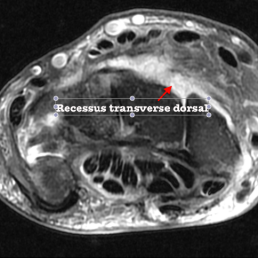

- Récessus transverse dorsal :

* entre la face dorsale de la tete/col du capitate, hamate et la capsule dorsale au niveau de la médio-carpienne ainsi que du pôle distal du scaphoïde